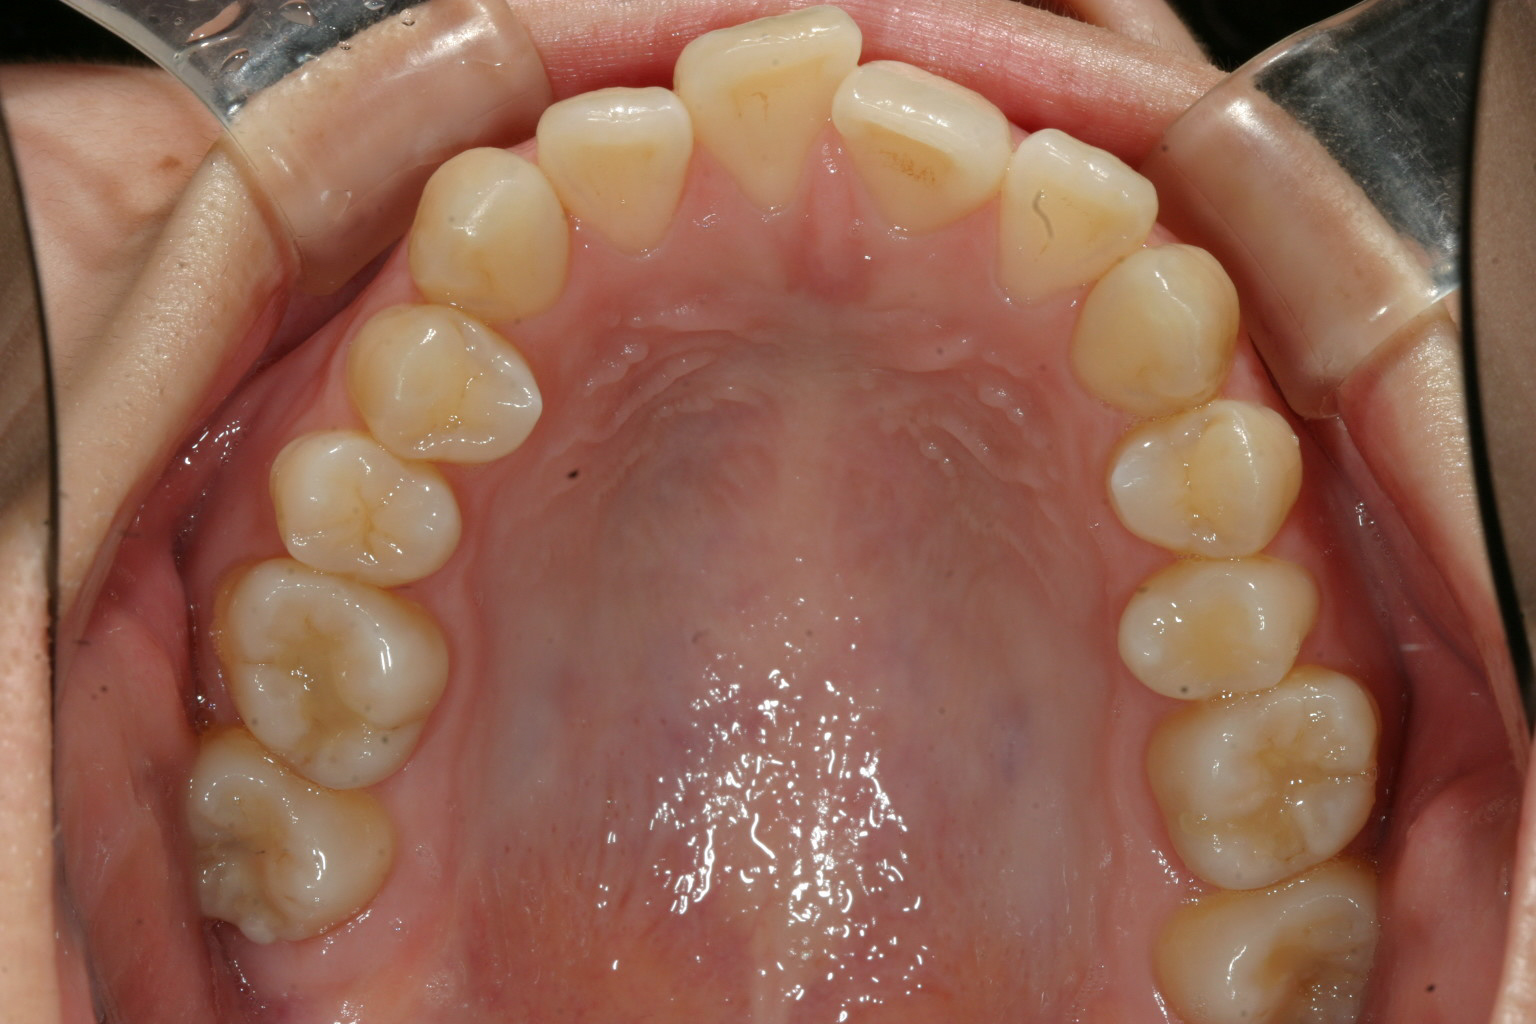

下の前歯は歯列がV字形の為4本の前歯が上手く並ばずガタガタになってます。

こちらも歯列をU字形にする事により綺麗に改善してます。

こちらの症例は典型的な症例で歯列形が悪い為の不正咬合です。

これって言って特別何をしたって事無く歯列を V字形をU字形にするだけでここまで改善します。